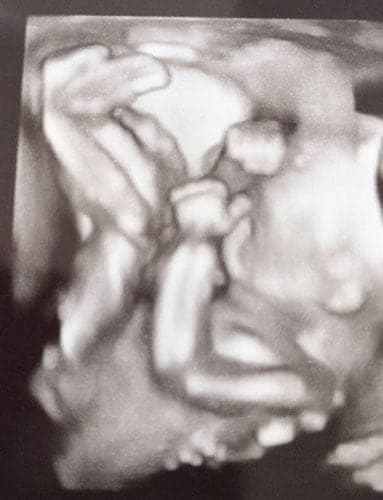

Ultraschallbilder aus dem 3. Trimester (29. bis 40. SSW)

Im dritten Trimester der Schwangerschaft ist das Baby so groß, dass es nicht mehr komplett auf ein Ultraschallbild passt. Nun kann man wunderbare 3D-Ultraschalle des Gesichts machen. In diesem Semester nehmen die Babys nochmal rasant zu und wer Glück hat, kann auf seinem Ultraschall schon erste Gesichtszüge erkennen.